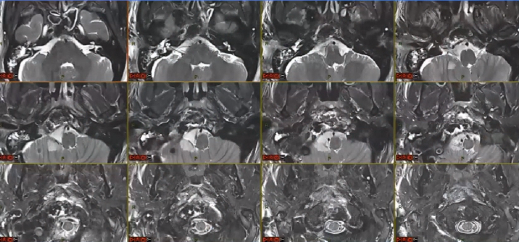

▼这个病例,它影响了颈1颈2,然后没有侵袭到硬膜内,我就不考虑用内镜了。考虑到脑脊液的释放等问题,这里我用了后外侧的一个入路。利用45度的内镜往上看,往上磨除岩骨的后方,可以一直暴露颈内动脉的岩骨段,然后海绵窦段。然后在显微镜下我们可以进行双手的操作,神经外科医生就比较熟悉的了。我们在做手术切除肿瘤切完了之后,还要进行固定。

▼这是一个较大肿瘤的案例,它严重影响到枕髁,我们用神经内镜,通过抽吸可以切除大部分,然后和显微镜配合。

▼这是术后的MRI